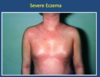

What does this photo show?

Severe Eczema

- erythredermic eczema

- acute eczema (red and weepy) is all over the skin’s surface

- patient is systemically unwell

- should be admitted to hospital

- likely to be staphylococcal infection

- colonises the skin

- perptuates eczema and can also cause infections